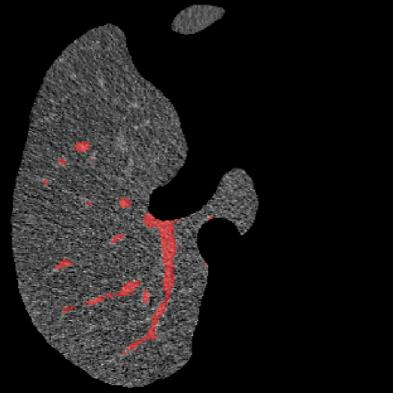

Manually segmenting the hepatic vessels from Computer Tomography (CT) is far more expertise-demanding and laborious than other structures due to the low-contrast and complex morphology of vessels, resulting in the extreme lack of high-quality labeled data. Without sufficient high-quality annotations, the usual data-driven learning-based approaches struggle with deficient training. On the other hand, directly introducing additional data with low-quality annotations may confuse the network, leading to undesirable performance degradation. To address this issue, we propose a novel mean-teacher-assisted confident learning framework to robustly exploit the noisy labeled data for the challenging hepatic vessel segmentation task. Specifically, with the adapted confident learning assisted by a third party, i.e., the weight-averaged teacher model, the noisy labels in the additional low-quality dataset can be transformed from "encumbrance" to "treasure" via progressive pixel-wise soft-correction, thus providing productive guidance. Extensive experiments using two public datasets demonstrate the superiority of the proposed framework as well as the effectiveness of each component.